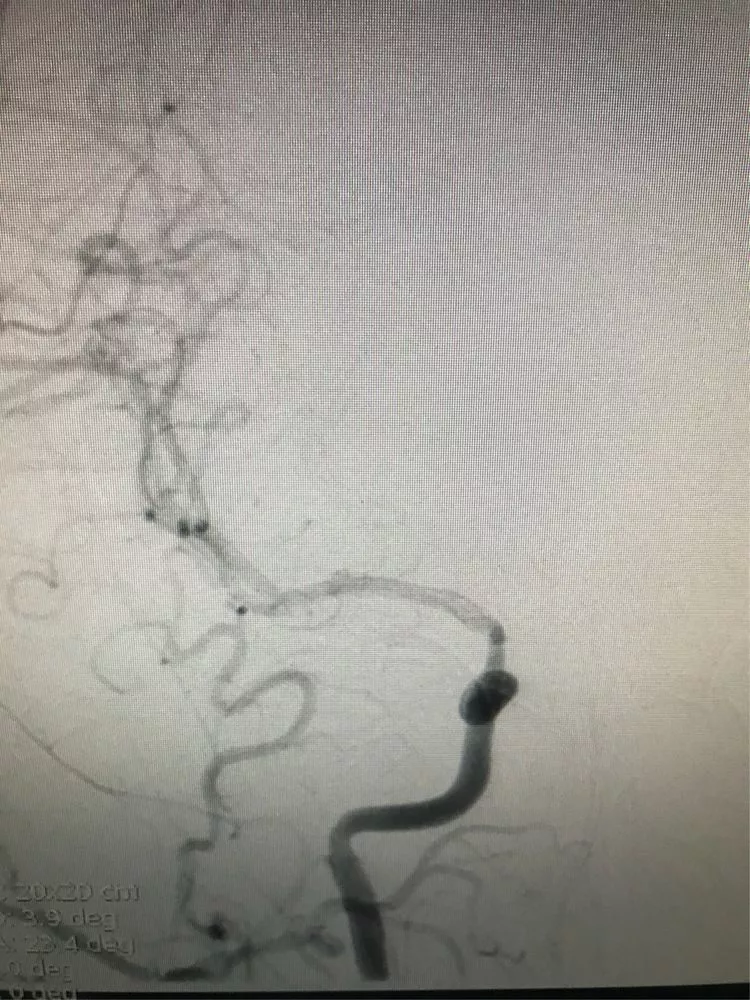

然后双导管交替填塞,小心啊!每填完一个弹簧圈都造影看双侧大脑前A2的血流通畅情况。

最后的影像。(瘤颈与前交通的切线位,没有弹簧圈突入前交通。)

正位,看双侧大脑前A2。